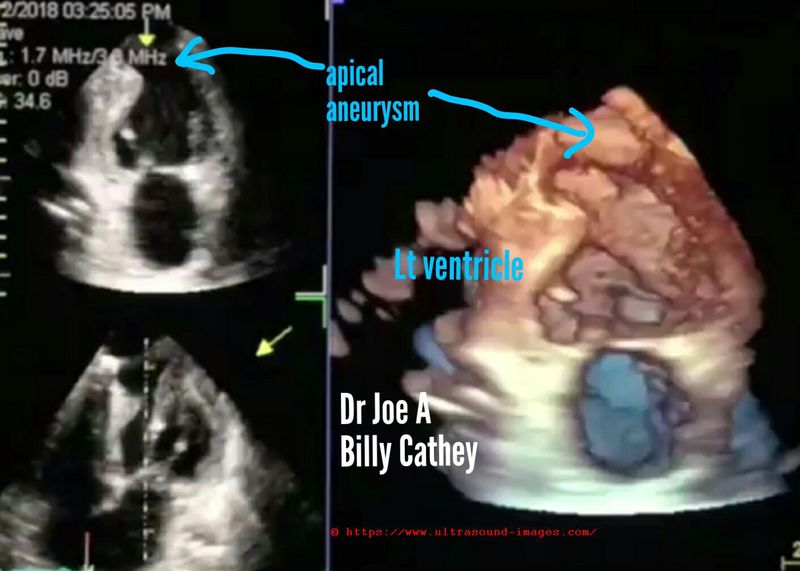

apical-aneurysm-left-ventricle

B-mode and contrast enhanced B-mode echocardiography (cardiac ultrasound) along with 3-D/ 4-D echo/ ultrasound show an aneurysm of the apical part of left ventricle (blue arrows). This type of aneurysm is the result of myocardial infarction involving the left ventricle resulting in weakening of the myocardium causing out-pouching or aneurysm formation in the apical region with each contraction or systole of the left ventricle.

Apical aneurysm of the left ventricle is the commonest site of aneurysm formation as a sequelae to myocardial infarction. (Images are courtesy of Billy Cathey).

D/d: pseudo-aneurysm of the heart--> pseudo-aneurysm results from rupture of the myocardium following a myocardial infarction with formation of a sac lined by pericardium. This type of lesion has no myocardial tissue lining the sac.

True aneurysms (like the case here), have lining of myocardium which can be traced to the adjacent part of the ventricle.